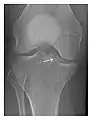

Occult osseous injuries may result from a direct blow to the bone by compressive forces of adjacent bones against one another or by traction forces during an avulsion injury. Lesions in the tibial plateau, hip, ankle, and wrist are often missed. In a tibial plateau fracture, any disruption of the posterior and anterior cortical rims of the plateau should be sought. Impaction of subchondral bone will appear as an increased sclerosis of the subchondral bone (Figure 1). In the hip, posterior acetabular fractures also present subtle radiographic findings. The acetabular lines should then be carefully examined keeping in mind that the posterior rim, which is harder to see on X-rays, is more frequently fractured than the anterior rim (Figure 2). In the wrist, detection of carpal bone fractures is often challenging, with up to 18% of scaphoid fractures radiographically occult. Carpal fractures, especially the scaphoid, are associated with the risk of avascular necrosis. In apparently normal wrist radiographs from symptomatic patients, if there is history of a fall on an outstretched hand with pain in the anatomic snuffbox, suggesting scaphoid injury, the initial examination with posteroanterior, lateral, and pronation oblique views must be complemented by other specific views such as supination oblique and the "scaphoid" view A careful examination of cortices for evidence of discontinuity or offset and cancellous bone for lucency is necessary (Figure 3).[1]

Figure 3: A 26-year-old man presenting with wrist pain after being assaulted. (a) Initial anteroposterior radiograph shows a subtle linear lucency within the scaphoid extending to the scaphocapitate articular surface that was overlooked (arrow). (b) Initial "scaphoid" view was negative. (c) Followup anteroposterior radiographs, 12 days later, shows obvious scaphoid fracture (arrows).[1]